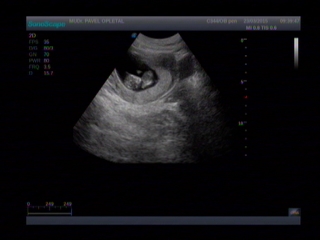

Ahoj holky. Tak dneska sme byli konecne zase na kontrole u doktora. Musela sem si rict ze chci fotku pidalky jinak by mi ani nedelal ultrazvuk. Pidalka je v poradku a ted cekame jeste na prvni screening. Tam jdeme 8.4. Tak snad taky bude vsechno v poradku. Musim se s vami podelit o nasi prvni fotecku :-) jinak nevolnosti uz polevuji tak snad uz bude jen lip.